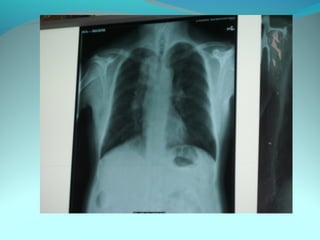

Opacité micronodulaire bilaterale diffuses et uniformement repartis

sur les 2 poumons realisant l’aspect d’une miliaire a petit grain

On note opacité latero trachiale ovalaire de 3cm de grand axe vertical

a limite ext des ADP médiastinale

Une opacité hilaire droite de 15 mm d’epaisseur

DIAGNOSTIC:

Miliaire tuberculeuse avec ADP mediastinal

Lymphome avec miliaire

Sarcoidose type2